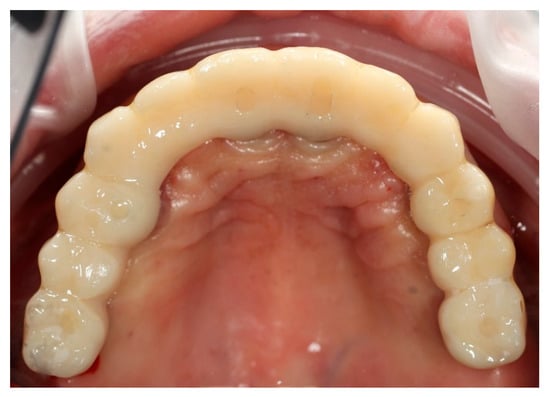

Figure 10. Digitally planned, 3D-printed full-arch provisional restoration after the healing phase and fixed to the multi-unit abutments screws, shown in situ (front view).

Finally, the prosthesis was delivered by fixing to the multi-unit abutments with screws. Clinical adjustments were performed to ensure perfect fit, occlusion, phonetics, and aesthetics. The patient reported immediate improvement in comfort and satisfaction compared to the acrylic splint (Figure 9 and Figure 10).

This early restoration provided stable occlusion, acceptable aesthetics, and proper phonetics while allowing progressive soft tissue conditioning. It also constituted the foundation for definitive prosthetic planning. The patient was instructed on hygiene maintenance and placed on a soft diet during the initial healing period.